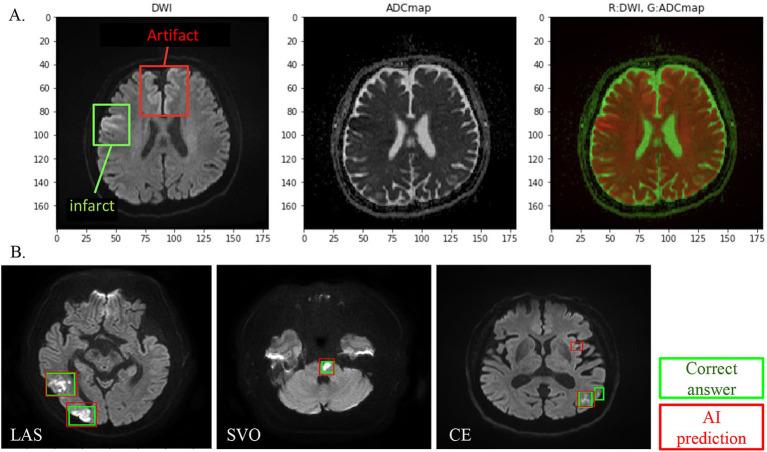

By utilizing multimodal data, such as DWI and ADC map images, as well as patient examination data, we were able to construct an AI that can explain the analysis results with a small amount of training data. Furthermore, the AI was able to classify with high accuracy (Cohort 1, evaluation data 88.7%; Cohort 2, validation data 86.1%).

通过利用多模态数据,如弥散加权成像(DWI)和表观扩散系数(ADC)图图像以及患者检查数据,我们能够构建一个仅用少量训练数据就能解释分析结果的人工智能。此外,该人工智能能够进行高精度分类(队列1,评估数据为88.7%;队列2,验证数据为86.1%)。